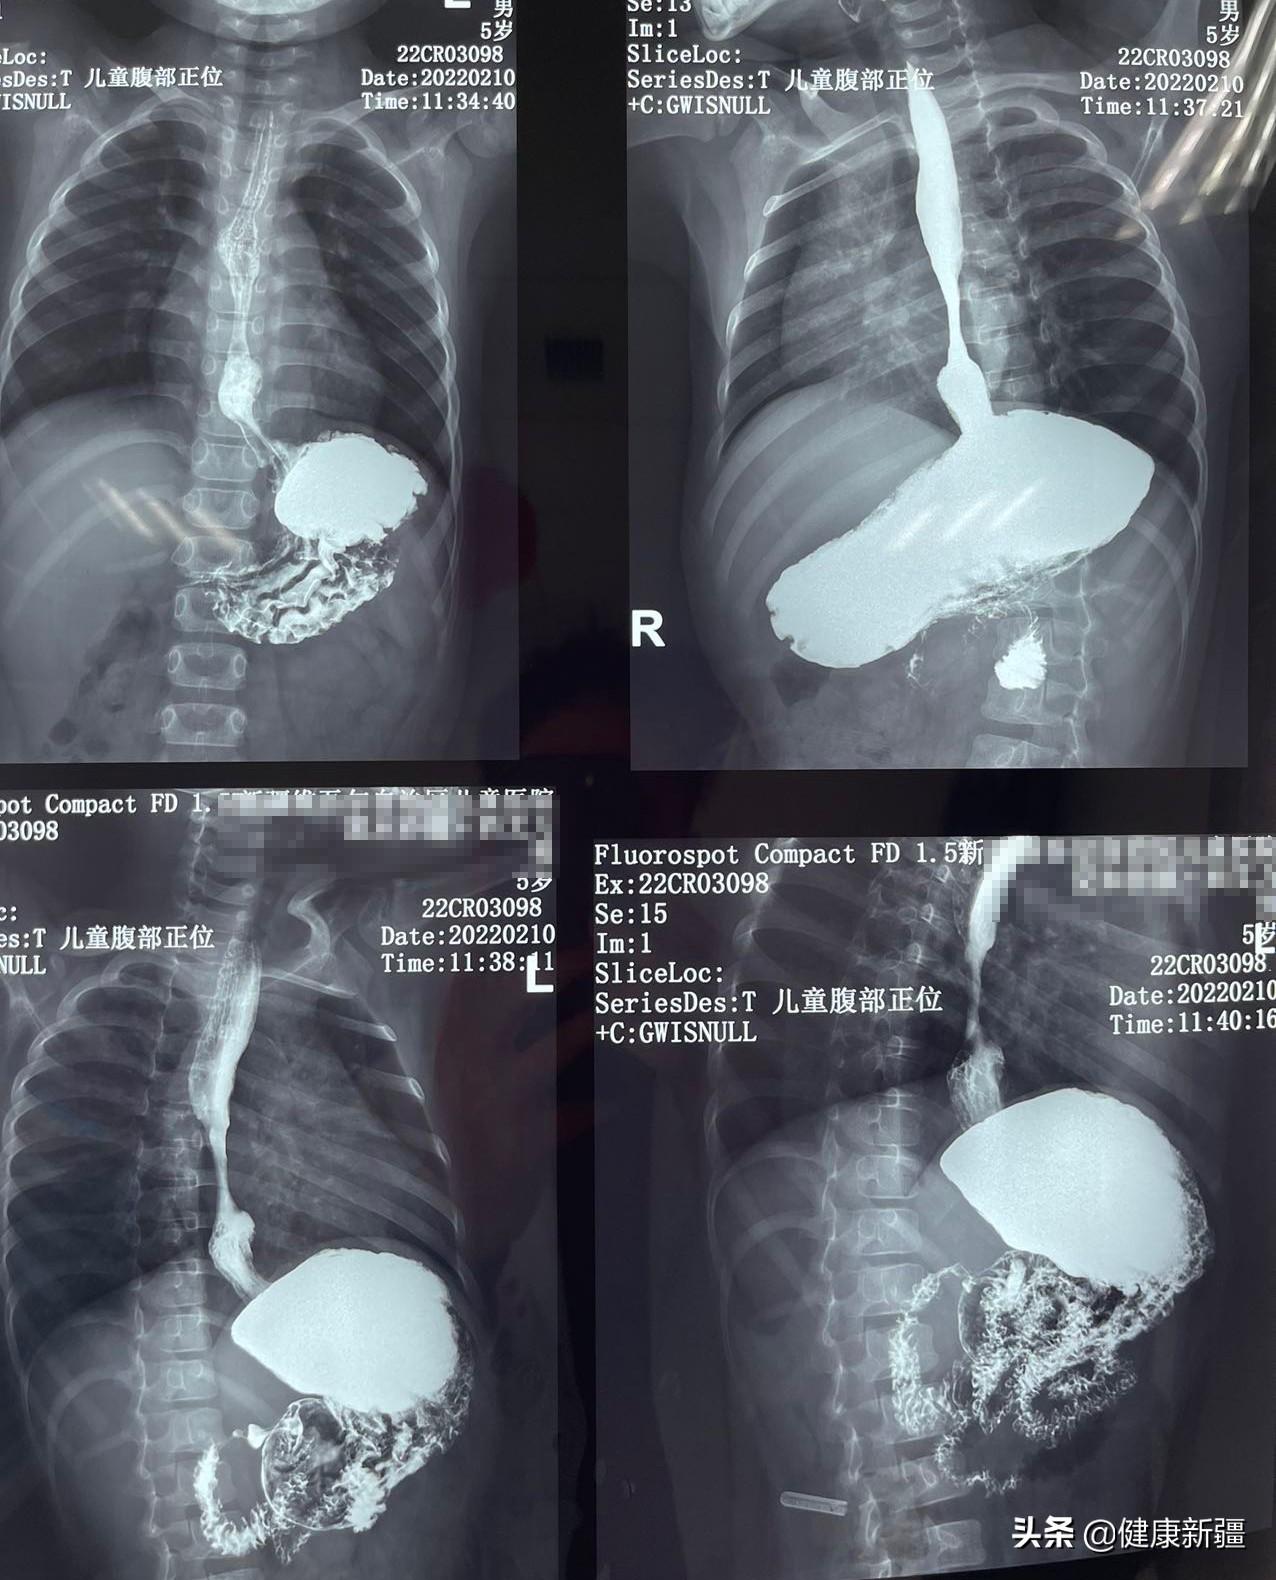

今年2月7日,面色苍白的小夏木来到北京儿童医院新疆医院就诊,完善相关检查,呼吸消化心脏科医生诊断为食管狭窄合并食管裂孔疝(巨大型),已出现重度贫血。结合患儿情况,呼吸消化心脏科给予药物治疗抑酸保护胃黏膜,同时给予营养支持和补铁治疗。

为了彻底解决这一问题,北京儿童医院新疆医院普外科进行了初步会诊后,将小夏木转至普外科病区,并给予完善食管24小时PH值监测。完善相关检查后,明确诊断小夏木是由胃食管反流引起的食管狭窄合并食管裂孔疝。

“胃食管反流病很常见,婴幼儿由于先天发育不全等问题,也会出现胃食管反流。”北京儿童医院新疆医院普外科主任和军表示,由于胃食管反流严重,导致部分食管面反复溃疡,最终形成食管狭窄并发食管裂孔疝。经食管24小时pH监测仪监测显示,小夏木的胃食管反流值监测数值高达176.9(正常值≤14.7),且食管病理性反酸以直立位为主,这在婴幼儿中非常少见,“长期口服抑酸药物,又阻碍铁的吸收,所以小夏木又出现了重度贫血。”